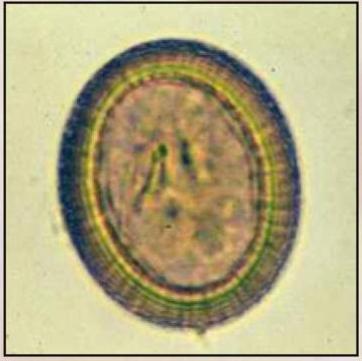

Barwniki do analiz parazytologicznych

Barwnik Fielda A i B:

• Barwienie kałów biegunkowych, aspiratów z dwunastnicy

• Nr kat 1482/1483

Barwnik Giemsa:

• Barwienie kałów nieformowanych, biegunkowych, aspiratów z dwunastnicy

• Nr kat 1484

Barwnik – Płyn Lugola (wodny roztwór):

• Wybarwienie zawartości komórek, na przykład jądra i mas glikogenu, pomagając w tym ich identyfikacji. Dodanie jodu zwiększa refrakcję jądra Endolimax nana, barwi peryferyjną chromatynę jądra gatunków Entamoeba i wykazują dobrze określoną masę glikogenu, która jest cechą torbieli niedojrzałych torbieli E. coli i torbielowatych Iodamoeba butschlii

• Nr kat 1486

Hematoksylina żelazista A i B:

• Wybarwienie na niebiesko z zróżnicowaniem szczegółów jądrowych

• Nr kat 1487/1488

Trichrom – barwnik dla Microsporidia:

• Zarodniki jajowate odbijają światło, ścianki jaskrawe różowo-czerwone. Tło zanieczyszczeń oraz bakterie- zabarwione kontrastowo zielonkawym kolorem

• Nr kat 1489

Trichrom – barwnik dla Protozoa:

• Nr kat 1490

Fuksyna karbolowa (Gram):

• Barwnik używany w technice Grama

• Nr kat 1495

Zieleń malachitowa:

• Zielony barwnik do różnicowania bakterii

• Nr kat 1501

Zmodyfikowany zestaw barwników do met. Cold Kinyoun:

• Komórki kwasowe barwią się na czerwono, tło i pozostałe elementy na niebiesko

• Nr kat 1503